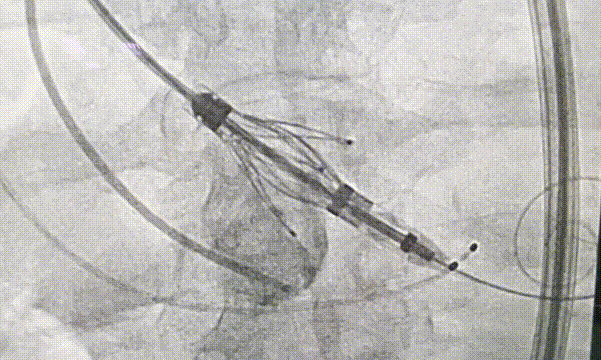

瓣膜释放过程